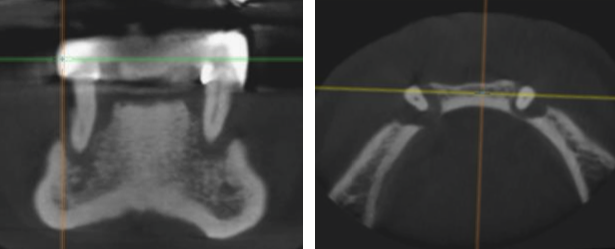

Secțiunea din CT-ul dentar inițial (Fig. 3.9.1, Fig. 3.9.2) în care se vede că singurii dinți restanți sunt cei 2 canini inferiori care nu mai prezintă implantare în os și deci nici stabilitate, fiind irecuperabili. După examenul radiologic și planificarea etapei chirurgicale s-au efectuat extracțiile și inserarea implanturilor. Acestea vor rămâne acoperite de gingie timp de 3-6 luni, perioadă necesară vindecării și integrării implanturilor în os.